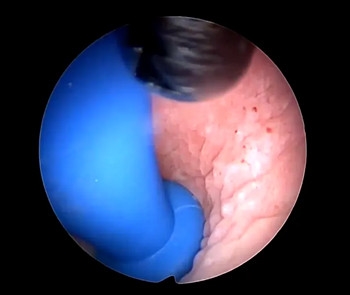

孟主任与小馨妈妈沟通后决定行全麻下宫腔镜阴道内镜技术,将阴道异物取出。

宫腔镜阴道内镜是一门较新的技术,该技术是宫腔镜技术的拓展。通过利用水流和内镜下视觉的指引,可直视观察宫颈管、宫颈内口等。宫腔镜阴道内镜下阴道内异物取出术一般为微创、无创手术。

孟主任利用宫腔镜专用异物钳

钳夹住硬币轻轻转动

松动后缓慢平稳的将银币转成斜位

将它慢慢取出